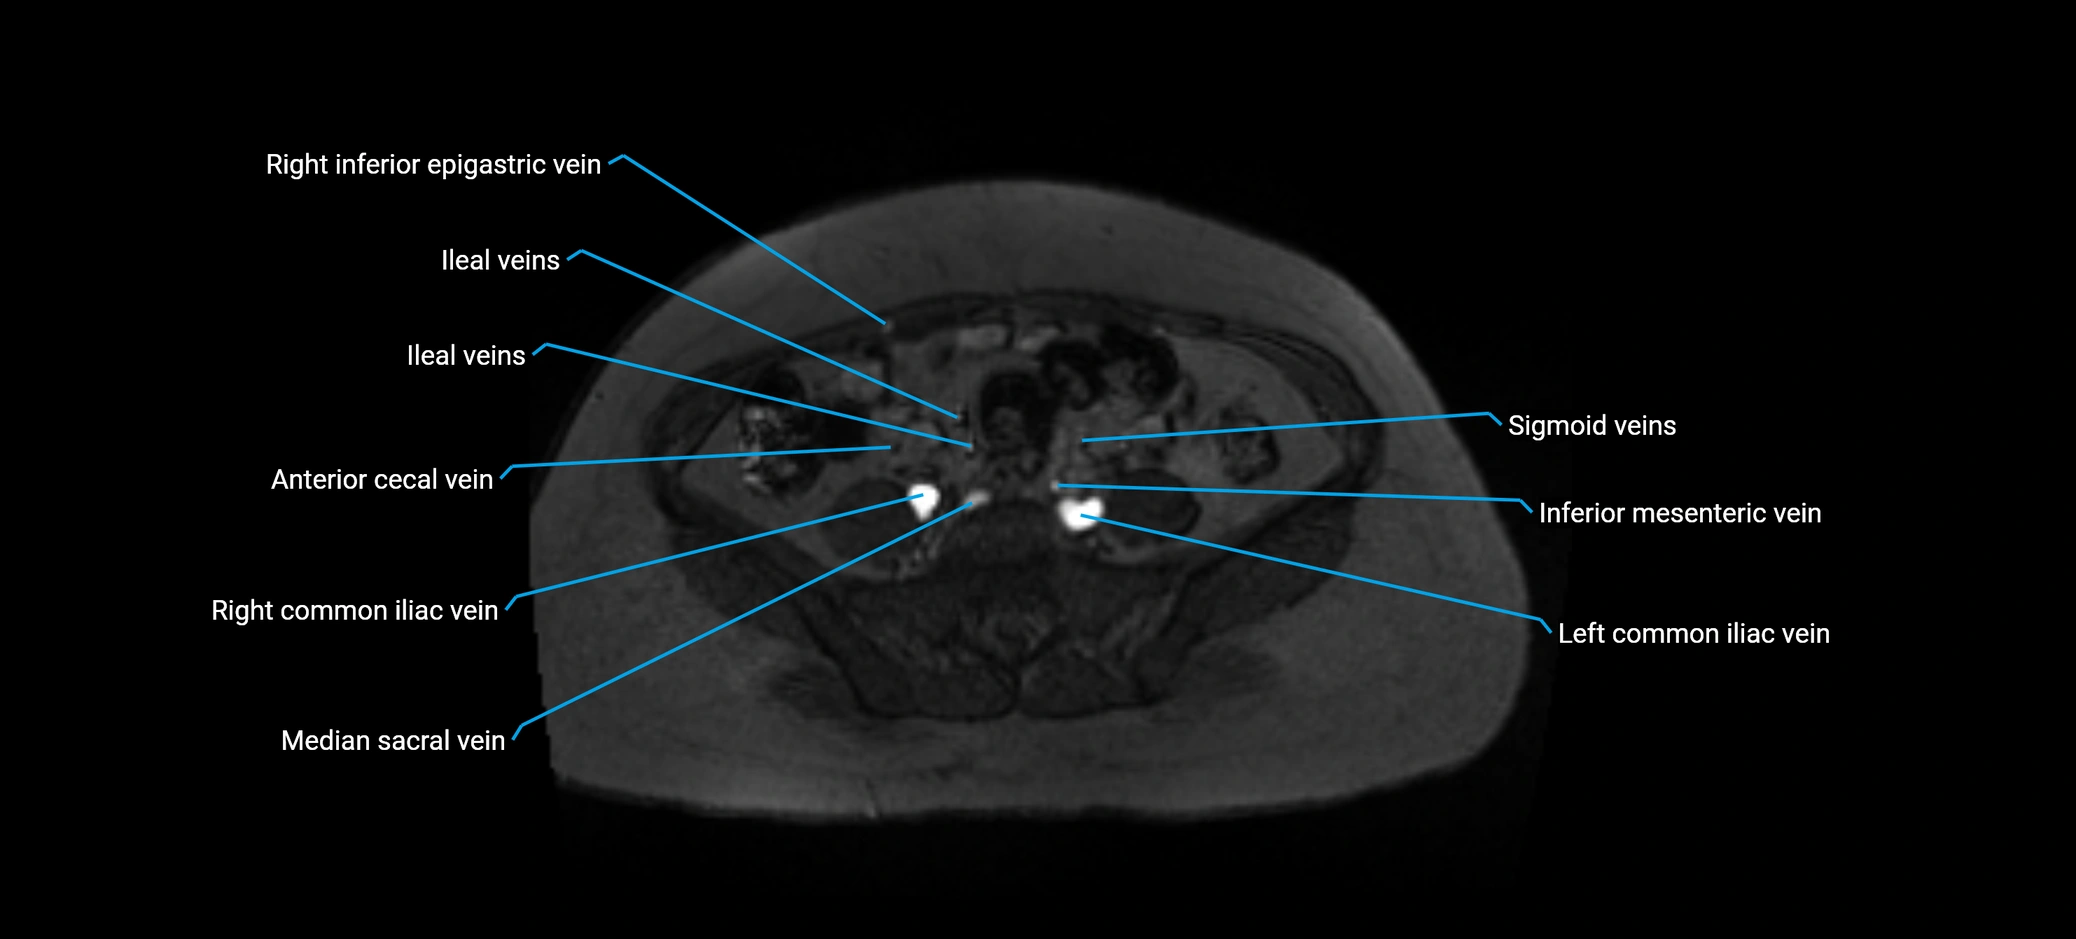

MRI image

image